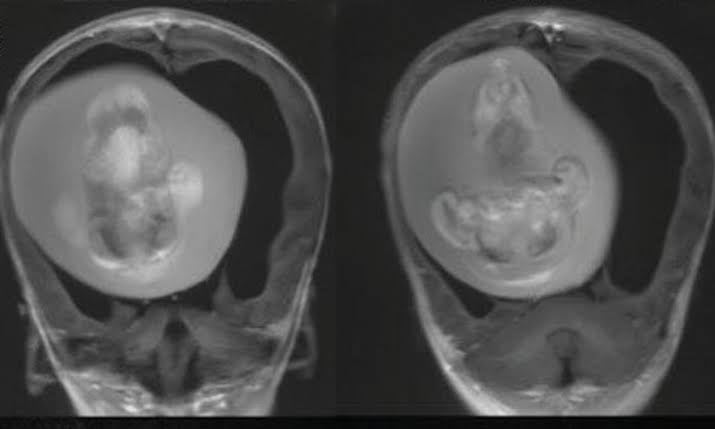

Doctors said the fetus had developed upper limbs, bones, and even fingernails, meaning it likely continued growing for months while inside its sibling in the womb.

The fetus which was about four inches long was only discovered when the parents took their daughter for hospital scans because she had an enlarged head and problems with motor skills.

CT scans revealed her unborn sibling was pressed against her brain.

Doctors said it had continued to survive a year after birth because it shared a blood supply with its sibling.